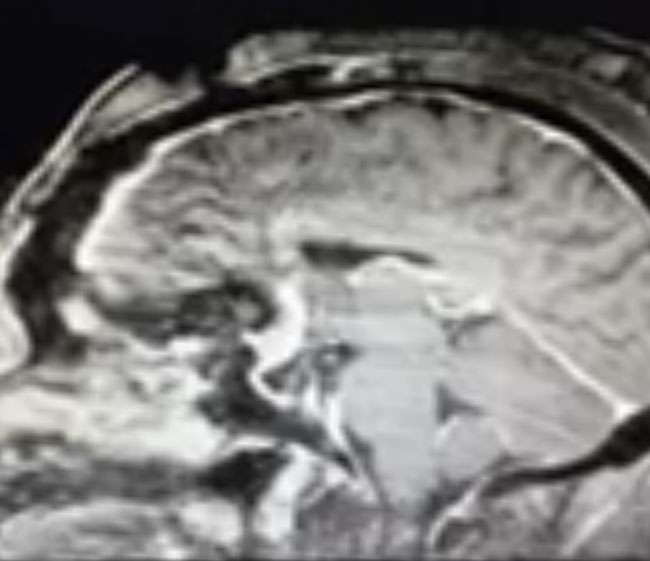

This is a 64 year-old woman with no significant past medical history who noted rapid deterioration of vision in her left eye 3 weeks earlier. She said it felt like there was a cloud over her eye. Ophthalmology evaluation confirmed poor vision in the left eye and ordered a brain MRI. The MRI demonstrated a large planum sphenoidale meningioma with significant compression on the optic nerves and optic chiasm and significant surrounding edema (Figures 1 a, b, and c). She was then referred to Dr. Michael Brisman for neurosurgical evaluation.